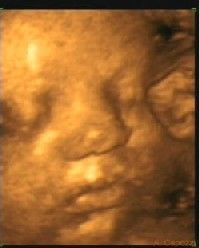

Il miracolo della vita

LONDRA (4 novembre) - I medici avevano deciso di sacrificarlo nell’utero di sua madre per non mettere in pericolo il gemello, visto che il suo cuore era troppo grande e lui invece non si sviluppava normalmente. Prima hanno tentato di tagliare il cordone ombelicale, ma non ci sono riusciti, poi hanno diviso la placenta in due convinti che sarebbe morto. Ma lui, Gabriel, non ne ha voluto assolutamente sapere e ora è un bel pupo di sette mesi, senza più i drammatici problemi di salute che minacciavano di farlo nascere morto.

La sentenza dei medici. «E’ davvero un miracolo!», esulta Rebecca Jones, la mamma, che si era lasciata convincere dai medici sulla «assoluta necessità» di sopprimere Gabriel prima della nascita. Trentacinque anni, consulente finanziaria, sposata a Mark, un venditore d’auto di 36 anni, Rebecca ha raccontato al tabloid "Daily Mail" la sua angoscia quando alla ventesima settimana di gravidanza i medici le hanno detto che le cose si mettevano male: uno dei due gemelli - il futuro Gabriel - aveva un cuore ingrossato, non si sviluppava e rischiava di morire da un momento all’altro con conseguenze altrettanto fatali per il fratellino. «Meglio porre fine alle sue sofferenze prima, piuttosto che dopo»: quest’argomento ha finito per far breccia nella donna che, alla 25ª settimana, ha autorizzato la soppressione del feto malato.

I tentativi per sopprimerlo. L’impresa però si è rivelata molto più difficile del previsto: i medici del Women’s Hospital di Birmingham non sono riusciti a tagliare in due il robusto cordone ombelicale e nemmeno la separazione della placenta in due ha impedito a Gabriel di alimentarsi. Gabriel ha tenuto duro e assieme all’altro gemellino - Ieuan - è stato senza ulteriori problemi dentro la pancia di mamma per altre cinque settimane, quando entrambi sono stati portati prematuramente alla luce con il taglio cesareo.

Tenace come Rocky: lo hanno soprannominato così. «Mi sono resa conto che Gabriel non aveva alcuna intenzione di mollare - dice la madre, che vive a Stoke-on-Trent - la mattina dopo l’operazione, quando ho sentito che tirava i calci. I medici non riuscivano a crederci quando hanno sentito il battito del suo cuore. E’ un miracolo!». A quanto sembra, il "miracolo" è stato reso possibile proprio dall’operazione che doveva concludersi con la morte di Gabriel. Grazie alla separazione in due della placenta il piccolo - subito soprannominato "rocky" (roccioso) per l’eccezionale tenacia dimostrata - ha infatti ricevuto più nutrimento dalla mamma e ha cominciato a svilupparsi normalmente. A sette mesi Gabriel pesa cinque chili e mezzo, non ha più problemi di cuore ed è perennemente appiccicato a Ieuan.